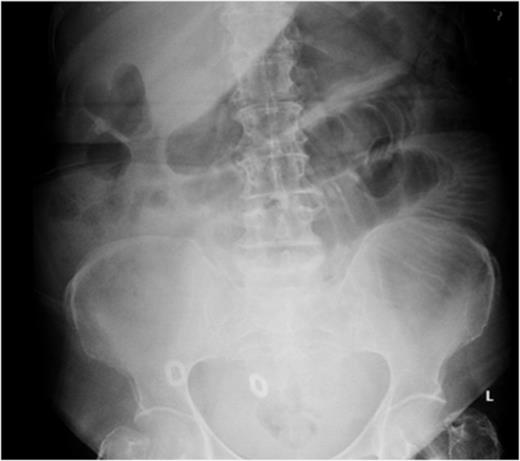

The second case described is of a 57-year-old gentleman who presented with a 3-day history of abdominal pain, vomiting and absolute constipation. His past medical history of note was a metallic aortic valve, although he was unable to give an accurate drug history on admission. On examination, his abdomen was distended with generalized abdominal tenderness and sluggish bowel sounds. Abdominal radiograph revealed dilated small-bowel loops (Fig. 3), and he was managed as a case of small-bowel obstruction, with intravenous fluid and a nasogastric tube.

Abdominal radiograph showing dilated small-bowel loops (Case 2).